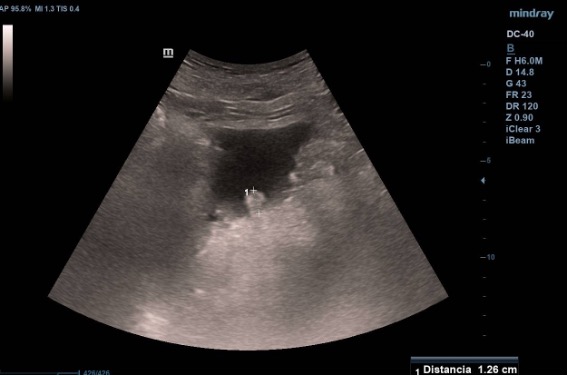

Ecografía vesical: Pared irregular, múltiples lesiones polipoides, la mayor (2.07 cm) en pared posteroinferior. Una lesión polipoiea dependiente de la próstata de 1,6 cm. Otra lesión más craneal en pared posterior de 1.26 cm, y cerca de uréter derecho una de 2 cm.  Además, varias lesiones polipoides más pequeñas en cara anterior y lateral derecha.